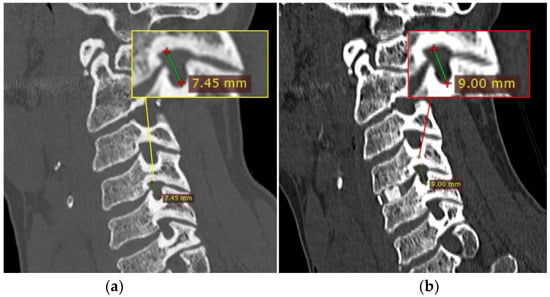

Figure 4.

Case illustration. Pre-(a, yellow box) and post-(b, red box) operative comparison of the foramen height (C-C diameter) at C4-C5, on the right side for illustrative purposes only, after the implant of a single-level cage.

Presenting symptoms included neck pain, radiculopathy and signs of cord involvement without gait impairing 14 patients (Nurick grade 0, I and II) and mild/moderate/severe myelopathic symptoms in 14 patients (Nurick grade III, IV, V or VI). According to mJOA score, no myelopathy was found in two patients, mild myelopathy (mJOA score from 15 to 16) in 10, moderate myelopathy (mJOA score from 12 to 14) in eight, and severe myelopathy (mJOA score from 0 to 11) in 8. An NRS and NDI evaluation between the pre- and post-operative period showed statistically significant results (p value < 0.001). (Figure 3) A negative correlation was confirmed between postoperative clinical outcome and postoperative disc height in its centrum measurement, and specifically −0.468 (p-value = 0.011) with the NRS scale and −0.603 (p-value < 0.001) with the NDI score. Complications of the ACDF procedure are not in the scope of this article, but we found that 60% of patients suffered mild temporary dysphagia and 15% suffered from slight temporary dysphonia. No postoperative hematomas or cage displacement were documented in our series. No permanent deficits were recorded, and temporary disturbances progressively regressed before discharge. An illustrative case is shown in Figure 4, comparing pre- and post-operative results. Table 4 shows patients’ demographic data, disease level, clinical pre- and post-operative grade, and a brief description of onset symptoms.